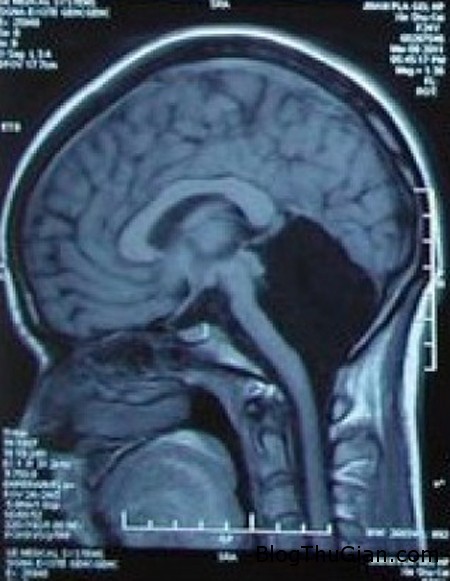

Hình chụp X-quang não bộ của cô gái 24 tuổi.

Theo đó, căn bệnh kỳ lạ của cô gái chỉ được phát hiện ra sau khi cô tới Bệnh viện Đa khoa PLA Trung Quốc tại tỉnh Quảng Đông, Trung Quốc để thăm khám về tình trạng nôn mửa và chóng mặt. Kết quả chụp CT và MRI cho thấy, não bộ của cô bị thiếu mất tiểu não, một phần não bộ, chịu trách nhiệm điều khiển các hoạt động, vận động thể chất của cơ thể. Nằm ở vị trí sau cầu não và hành tủy, tiểu não chứa khoảng nửa nơ-ron thần kinh não bộ.